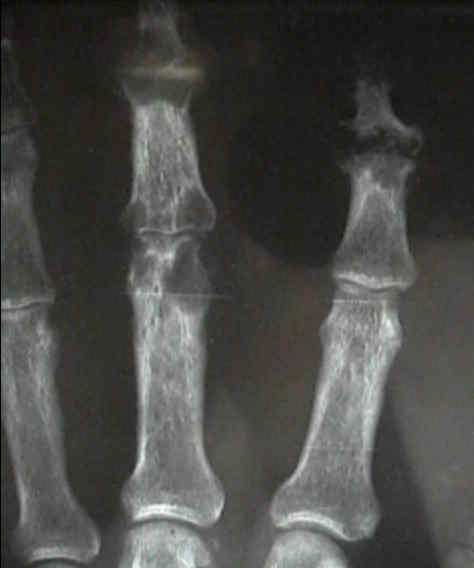

- in the hand look for oval periarticular erosions;

- multiple erosions will be distributed throughout the carpi and phalanges bilaterally;

- erosions have sclerotic borders and will often have overhanging edges;

- unlike classic RA, in early gout, hand and wrist joints will have preserved joint spaces and normal mineralization;

- case of histologically proven gout involving the proximal 5th metatarsal: